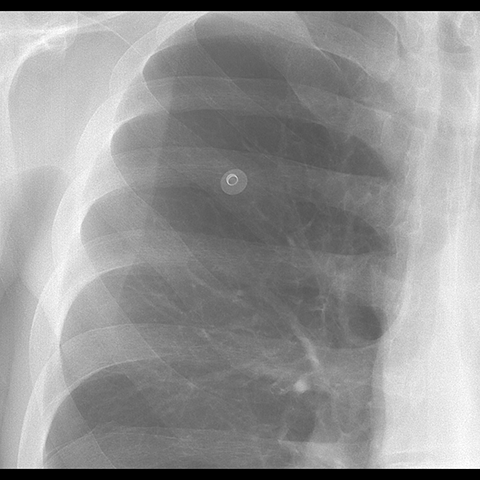

A 62 year-old male presents with chronic shortness of breath (Frontal Radiograph). [2 of 6]